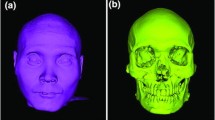

The colour coded distance maps between the best-fit approximated segmented and directly scanned facial surface models revealed consistent outcomes within and between acquisition settings, with deviations from the true model only locally reaching a maximum of 0.5 mm (Fig. 8). Large deviations were consistently present at the sides of the skull, located distant to the used superimposition reference area.

This study tested the accuracy of both CT and CBCT radiographic scanners, using regular radiation dose settings and a low radiation setting, offered by one CBCT unit. The image acquisition protocols were defined according to the standard practice for the assessment of craniofacial morphology, by specialist radiologists that were regularly using the radiographic machines for clinical purposes. All tested methods performed similarly, exhibiting an average trueness of 0.12 mm, without any significant difference between machines or settings. Colour coded distance maps revealed local deviations extending up to 0.5 mm, but the overall models were robust in all cases, despite the different image acquisition configurations. This finding has significant implications when 3D surface models are sought for diagnosis, growth or treatment outcome evaluation, or applications such as virtual surgical planning and manufacturing of prostheses in maxillofacial surgery. In every circumstance, whether these accuracy levels are acceptable or not, depends on the specific research or clinical context in which they are intended to be applied. The present findings showed that imaging methods applying lower radiation than the conventional CT can provide adequate digital models for the assessment of facial morphology, without compromises in accuracy. This holds true even for the low dose acquisition with the Planmeca CBCT scanner, which was performed using half of the radiation dose of the regular scan by the same unit. In the same line, a previous qualitative study evaluating the visibility of selected anatomical structures of the jaws in large FOV CBCT images with lower exposure settings showed encouraging results33.

The overall trueness of 0.12 mm was very high when considering the magnitude of the optical scanner error22 and the segmentation error, at 0.03 mm and 0.07 mm, respectively. Larger deviations up to 0.5 mm were consistently present at the sides of the skull, which were distant to the selected superimposition reference area3,10,22,34, as well as to local sites over the entire tested surface, with no specific spatial pattern. The latter findings might be partially attributed to direct optical surface scanner inaccuracies that might sometimes exceed 0.2 mm locally20,22.